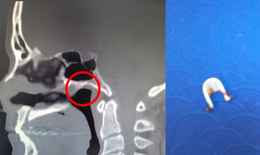

Hy hữu: ‘Bỏ quên’ hai đoạn đũa trong hốc mũi hơn một năm

Tin nóng y tế - 02/07/2025 13:41SKĐS - Ngày 2/7, Bệnh viện Tai Mũi Họng TPHCM cho hay, các bác sĩ nơi đây vừa xử trí thành công ca “trục xuất” dị vật hy hữu là 2 đoạn đũa bị bỏ quên trong hốc mũi nam bệnh nhân hơn một năm.